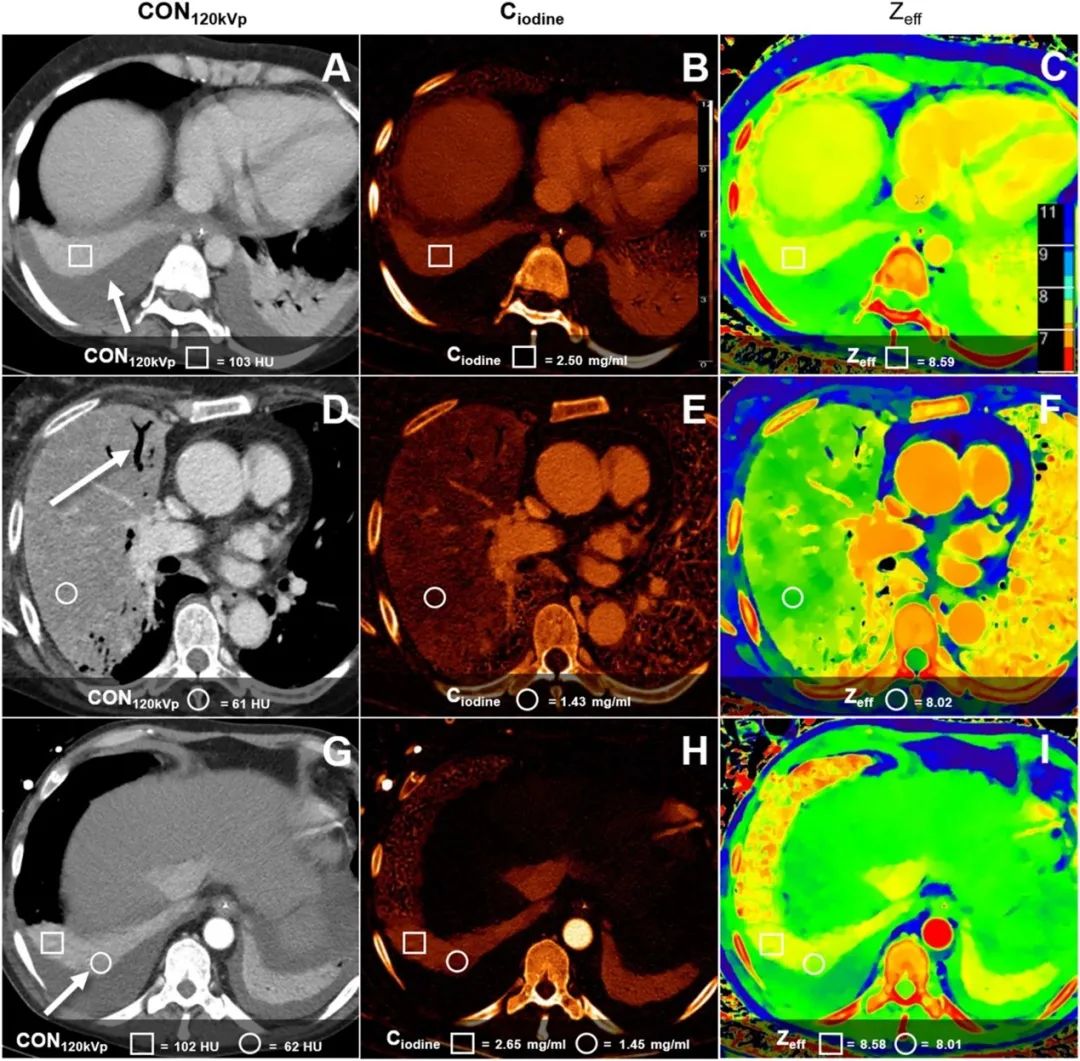

造影劑增強胸部CT中的肺實變:肺不張和肺炎鑒別中光譜檢測器計算機斷層成像參數(shù)的應(yīng)用

德國海德堡大學醫(yī)院Philip Konietzke團隊發(fā)表研究成果。研究目的:研究肺不張與肺炎的增強胸部CT鑒別中,光譜檢測計算機斷層成像(SDCT)參數(shù)的定量區(qū)分價值。材料和方法:他們對63名患者進行了靜脈期對比增強SDCT掃描,其中22名肺炎患者,41名肺不張患者。運用感興趣區(qū)分析,在常規(guī)重建(CON120kVp)上測量CT值(HU),在光譜重建上測量碘濃度(Ciodine,mg/ml)和有效原子數(shù)(Zeff)。利用ROC分析和對比噪聲比(CNR)評估不同重建在區(qū)分肺不張和肺炎時的潛力。研究結(jié)果:在增強SDCT中,CON120kVp、Ciodine和Zeff圖像在肺不張和肺炎鑒別上差異顯著(P < 0.001)。在CON120kVp 圖像上,81HU閾值識別肺炎的敏感性為93%,特異性為95%;Ciodine和Zeff圖像的敏感性相同,但特異性較低,分別為85%和83%。CON120kVp圖像顯示正常肺與肺不張或肺炎之間的CNR明顯較高,分別為30.63和27.69,Ciodine圖像的CNR分別為3.54和1.27,Zeff圖像則分別是4.22和7.63(P <0.001)。在無造影劑情況下,所有參數(shù)都無法區(qū)分肺不張和肺炎。研究結(jié)論:根據(jù)光譜參數(shù)Ciodine和Zeff,造影劑增強SDCT可以鑒別肺不張和肺炎。然而,與CON120kVp圖像上的CT值測量相比,光譜參數(shù)的測定并沒有更大的價值?;赟DCT定量參數(shù)的鑒別仍然需要造影劑。